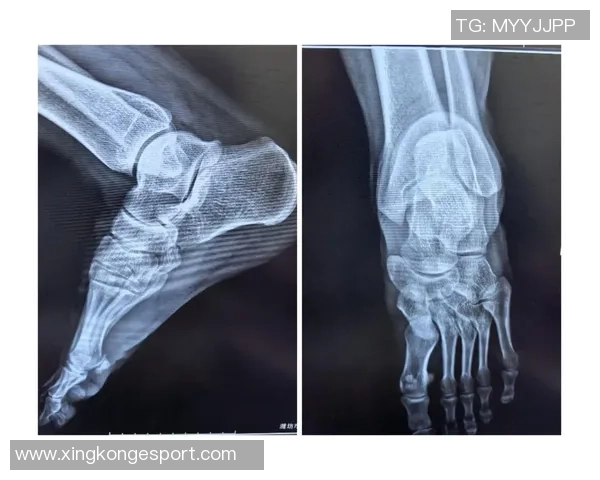

X光检查虽然排除了骨折的可能性,但这并不意味着博伊尔斯不会面临长期康复的问题。医生指出,他可能存在软组织损伤,这类损伤往往恢复期较长,并需要专业的治疗与康复训练,以确保完全愈合。